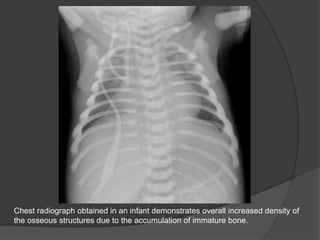

Chest radiograph obtained in an infant demonstrates overall increased density of

the osseous structures due to the accumulation of immature bone.

Chest radiograph obtainedin an infant demonstrates overall increased density of the osseous structures due to the accumulation of immature bone.